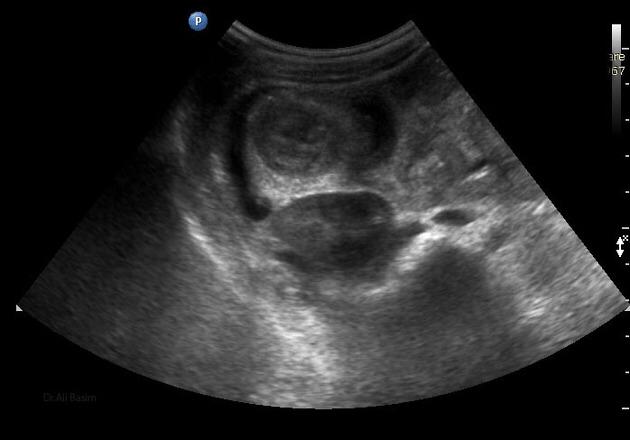

La invaginación intestinal es la causa más común de obstrucción intestinal en niños de 3 meses a 3 años. Se caracteriza porque un segmento de intestino penetra en otro segmento intestinal. Puede presentarse en colon, intestino delgado o entre intestino delgado y el colon. El resultado es la obstrucción intestinal.